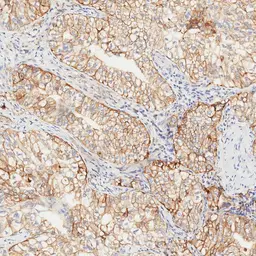

IHC-P analysis of human oral cavity squamous cell carcinoma (OCSCC) tissue using GTX639925 PD-L1 antibody [H302] HistoMAX™.

Strong predominantly membranous PD-L1 positivity of all tumor cells of a squamous cell carcinoma of the oral cavity. Some inflammatory cells are also PD-L1 positive.